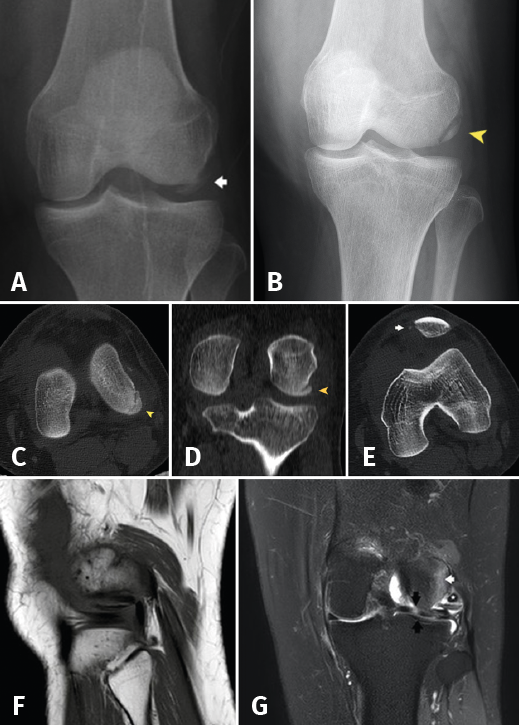

The initial radiographs revealed fracture of the external femoral condyle with an osteochondral fragment lodged in the lateral femorotibial joint space (Figure 1A). This displacement was not confirmed at radiological controls following immobilization (Figure 1B). Computed axial tomography (CAT) revealed a non-displaced double fracture line at the posterior margin of the external femoral condyle, parallel to the joint surface of the latter and measuring 21 mm in length, together with signs of avulsion fracture at the medial margin of the patella, with lateral subluxation (Figure 1B).

Figure 1. A: anteroposterior radiograph of the left knee. Osteochondral fragment of the external femoral condyle (arrow); B: reduced fragment in the initial anterosuperior radiograph (arrowhead); C: axial view; and D: coronal view of the initial CAT scan showing the osteochondral fracture without displacement (arrowhead); E: CAT coronal view showing fracture avulsion at the medial margin of the patella, with lateral patellar subluxation due to involvement of the medial retinaculum (arrow); F: MRI sagittal view showing the fragment and tendon of the TP; G: MRI coronal view showing bone edema of the external femoral condyle (white arrow) and subluxation of the TP (asterisk), together with horizontalization of the osteochondral fragment and a hyperintense image corresponding to rupture in the external meniscus with a pseudodiscoid appearance (black arrows).

At reassessment after 12 weeks, the patient reported "joint laxity" and "failing" of the knee. The physical examination revealed altered gait with great patient apprehensiveness and a tendency towards a "varus drive" pattern, overjet in the lateral femorotibial compartment with mild laxity +/+++ in varus and 0 and 30 degrees of flexion, together with an inconclusive dial test. The Lachman and anterior and posterior drawer in neutral rotation manoeuvres proved negative. The posterolateral rotary drawer test showed subtle asymmetry, with a joint balance of 0 at 115 degrees. The MRI study revealed a subchondral lesion in the loading zone of the external femoral condyle accompanied by intense bone edema and joint effusion. The external meniscus presented a pseudo-discoid appearance with suspected rupture (Figure 1C-D).